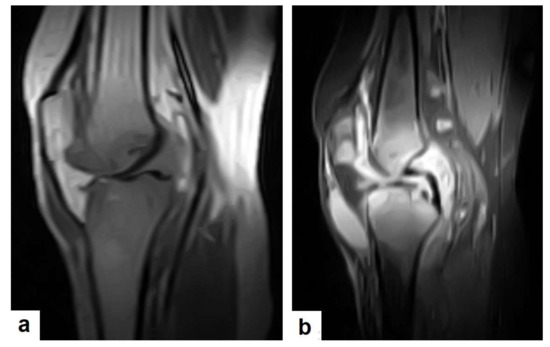

Figure 24. Knee TB in a 45-year-old patient with proved case of knee TB infection. Selected sagittal MRI images of (a) T1-weighted image and (b) T2-weighted image show extensive oedema of the articular surfaces of the knee, appearing as low signal intensity on T1 and high signal intensity on T2 with diffuse synovial thickening and large bone erosions (arrow heads), with mild joint effusion and a prepatellar pocket of fluid collection, which appear as low signal intensity on T1 and high signal intensity on T2. In addition, multiple enlarged popliteal lymph nodes were present.

2.7. Musculoskeletal (MSK) TB

TB can affect any part of the musculoskeletal (MSK) system, and symptoms of TB may be insidious, causing TB not to be considered. CT and MRI imaging modalities can bring suspicion to TB diagnoses [57]. MSK TB has a wide range of radiological features that can mimic many pathologies all over the body. However, radiological assessment is often the first step in the diagnosis of MSK TB [58]. The most common type of MSK TB is tuberculous spondylodiscitis (Potts disease), which accounts for 50% of MSK TB [57,58] (Figure 18 and Figure 19). Osteoarthritis TB affects joints or bones. It usually affects long weight-bearing bones and sometimes affects the ribs. Articular TB usually presents as monoarthritis in the knee (Figure 24) or the hip joints. However, sacroiliac, and sternoclavicular joints are also sometimes affected. The predilection of TB to affect the vertebrae and the large joints is due to the rich blood supply to the vertebrae and the growth plates of the long bones [59]. TB arthritis presents as a slow progressive destructive monoarthritis, so the diagnosis is delayed due to the indolent onset and low clinical suspicion [60].

On medical imaging, TB may initially show soft tissue swelling and later progress to periosteal thickening, osteopenia, periarticular bone destruction, and cold abscesses, and fistulae may develop in late cases. MSK TB is a differential diagnosis of a wide bone lesion. At the early stages, it is often misdiagnosed as traumatic lesions, degenerative joint disease, gout, pseudo gout, rheumatoid arthritis, or pigmented villonodular synovitis. High suspicion of TB is required, and a final diagnosis can be carried out by using arthrocentesis and a mycobacterial culture; in addition, a synovial biopsy is often needed [59,60].